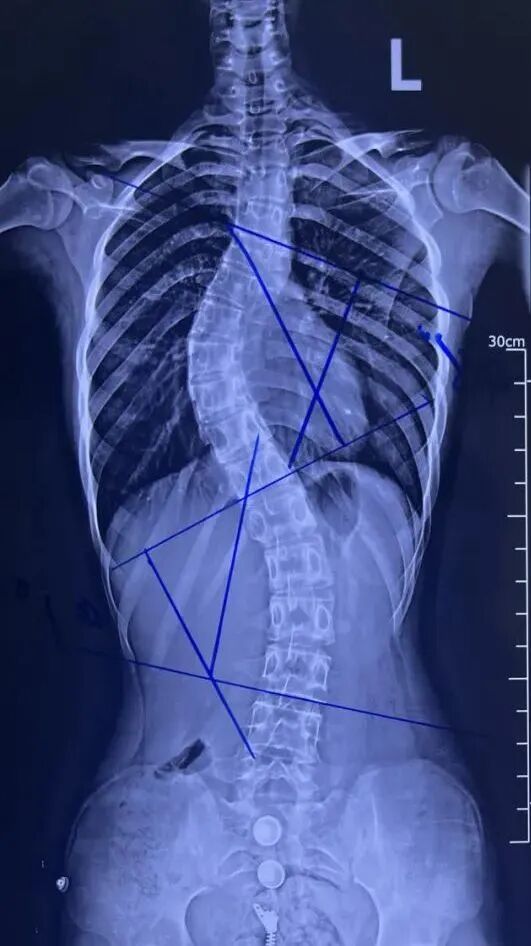

青少年脊柱侧弯是指脊柱在冠状位上偏离中线,出现弯曲或扭曲的现象。

脊柱侧弯示意图